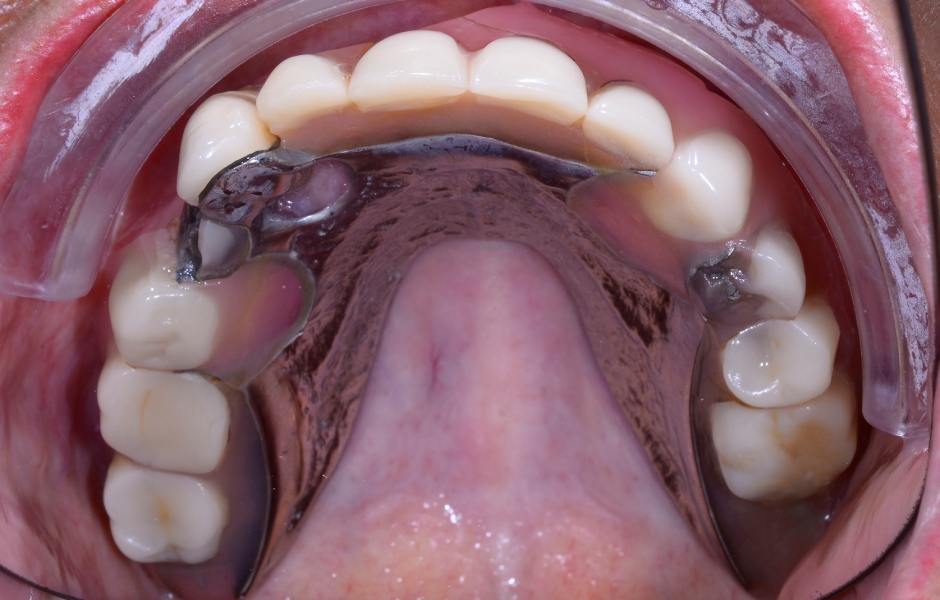

Abutmenty SKY uni.cone (bredent medical) byly zavedeny přímo skrze rozdělenou spodní část stohovatelné šablony v souladu s konceptem One-Time Therapy. Díky tvarově přesnému spojení jsou laterální síly z můstku přenášeny přímo na abutment, čímž se minimalizuje riziko povolení šroubů a fraktur.

Pro protetickou dostavbu byly v pozicích 11 a 21 použity rovné abutmenty a v ostatních pozicích angulované (17,5 °) transverzálně šroubované abutmenty. Veškeré další kroky bylo možné provádět na úrovni abutmentů, což umožnilo stabilizaci krestální kosti a neiritující cirkumferentní formování měkkých tkání.

Obr. 5: Plánované implantáty z hlediska velikosti, délky a orientace.

Obr. 6: Návrh a výroba modulární chirurgické šablony s okluzálně-palatinálními vstupy pro šrouby.

Obr. 7: Návrh a výroba modulární chirurgické šablony s okluzálně-palatinálními vstupy pro šrouby.

Obr. 8: Návrh a výroba modulární chirurgické šablony s okluzálně-palatinálními vstupy pro šrouby.